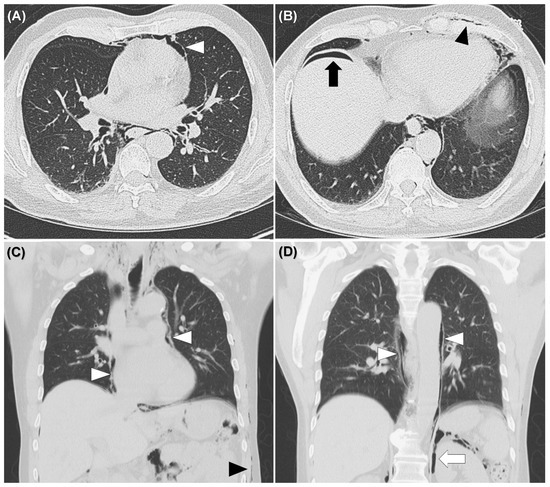

Figure 4. Non-enhanced computed tomography of the chest showed pneumomediastinum (white arrowheads) (A,C,D), subcutaneous emphysema (black arrowheads) (B,C), pneumoperitoneum (black arrow) (B), pneumoretroperitoneum (white arrows) (D), but no evidence of rib fracture and pneumothorax.